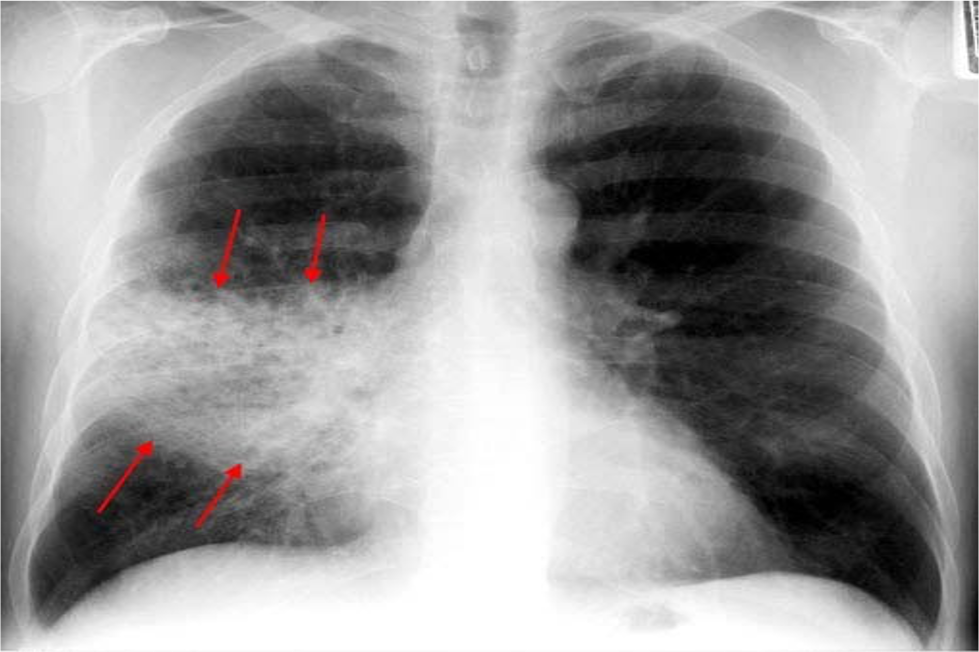

What features are seen on this CXR? What is the likely diagnosis?

Airspace fluffy shadowing

Pneumonia